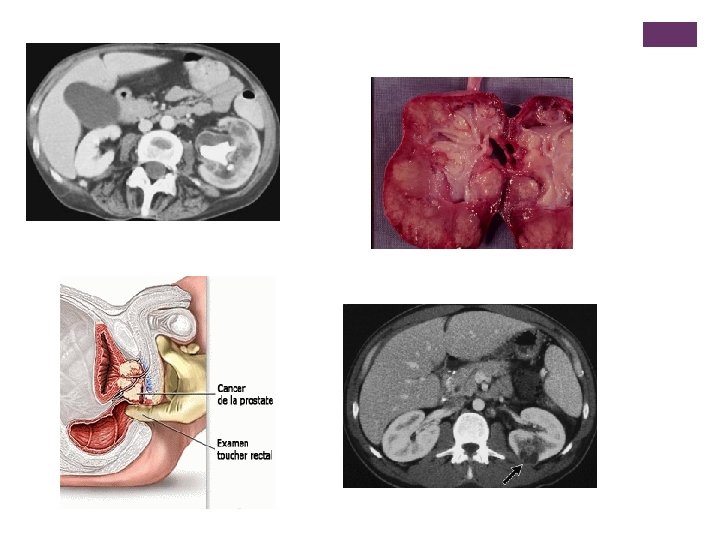

+ La pyélonéphrite n Signes de cystites inauguraux parfois discrets et qui peuvent manquer. n Début souvent brutal : par lombalgie unilatérale + fièvre + frissons n Forme avec signes digestifs au premier plan n Forme « larvée » du sujet âgé n Formes compliquées : n n Bactériémie et choc septique Abcès du rein

+ La prostatite , l’orchi-épidydimite n Signes fonctionnels bas n + fièvre et frissons n + douleur ou pesanteur pelvienne n + RAU n + / - orchite n Peu de symptômes dans les formes chroniques

+ Autres examens n NFS , iono + créat n Hémocultures n Echographie rénale et prostatique si pyélonéphrite ou prostatite : n n Recherche d’obstacle , d abcès , de malformation … URO – TDM : parfois pour préciser anomalie échographique